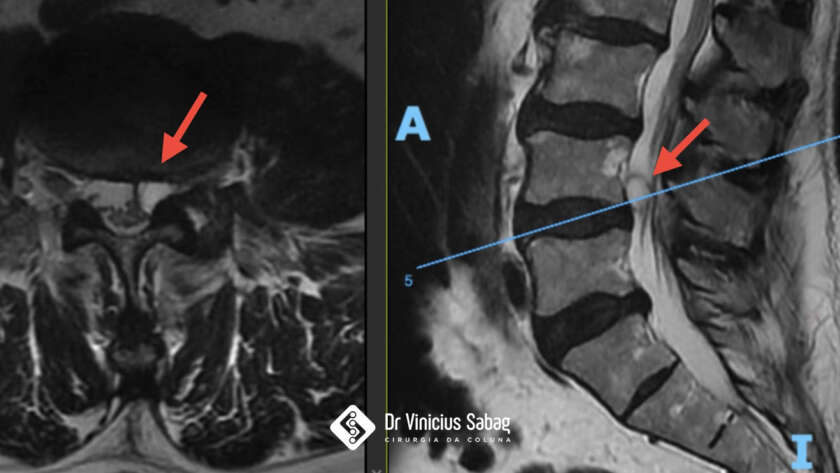

Paciente masculino, 49 anos, com início de dor lombar há 6 meses, associada à irradiação para o membro inferior direito.

Nesse período, realizou diversas tentativas de tratamento conservador, incluindo uso de medicações, fisioterapia contínua e mesa de tração, porém sem melhora dos sintomas.

As dores intensas e progressivas estavam limitando suas atividades diárias…